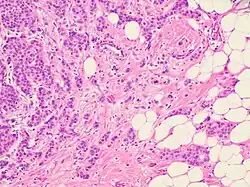

Histopathologic criteria

On microscopic evaluation carcinomatous cells are seen below the basement membrane of lactiferous ducts and invade into the surrounding breast stroma. Otherwise, there are no specific histologic characteristics, essentially making it a diagnosis of exclusion.[21] The histopathologic characteristics seen in these lesions are heterogenous. The cells of a lesion of invasive carcinoma NST may retain >70% ductal differentiation or appear completely undifferentiated. The tumor cells may be arranged in sheets, nests, cords, or singly distributed. They are pleomorphic (i.e., vary in size and shape). They usually have prominent nucleoli and multiple mitotic cells per magnified field of view, which are features generally consistent with cancerous cells. The surrounding non-ductal tissue, known as stroma, can range from none to abundant.[22][23]

Small inclusions of special features may be present within an invasive carcinoma NST tissue sample, but will be 'limited' (ie <10%). Carcinomas of mixed type will have a specialized pattern or lobular carcinoma in the majority (ie at least 50%) of the tumor and a non-specialized pattern in between 10-49% of the sample. Thus, such tumors will be called mixed invasive NST and special type or mixed invasive carcinoma NST and lobular carcinoma.[24]

Histopathology of invasive ductal carcinoma of the breast representing a scirrhous growth. Core needle biopsy. Hematoxylin and eosin stain. Invasive ductal carcinoma of the breast. H&E stain.